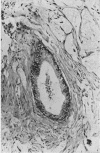

Ten cases of mucocele of the vermiform appendix are described. Eight cases were of mucinous cystadenoma of the appendix and six cases showed acute inflammation. Two of the six cases showed pseudoinvasion of the appendix and in a further case the appendix had perforated with extrusion of a misplaced neoplasm. Two cases were of mucinous cystadenocarcinoma and one of these was diagnosed as `pseudomyxoma peritonei'. `Pseudomyxoma peritonei' is a misnomer and is caused by dissemination of a mucinous cystadenocarcinoma within the peritoneal cavity. The special problems of histological diagnosis are discussed.